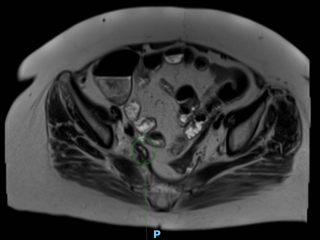

Case presentation

A 65-year-old woman with rectal adenocarcinoma (pT4bN0R2, KRAS-mutated) treated with neoadjuvant chemoradiotherapy, and extensive pelvic surgery developed chronic right-sided ureteral obstruction requiring long-term ureteral stenting. From 2023 onward, she experienced recurrent episodes of pyelonephritis, with urine cultures repeatedly isolating enteric organisms. In 2025, pelvic magnetic resonance imaging and retrograde ureteropyelography revealed right-sided hydronephrosis and a fistulous tract connecting the distal right ureter and the rectosigmoid colon, without evidence of tumor recurrence. Surgical management consisted of a bloc resection of the fistula, proctectomy with perineal closure, right ureteral reimplantation, terminal colostomy, and omentoplasty. The postoperative course was uneventful.